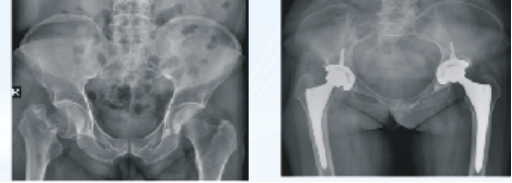

人工髋关节置换术

适用:股骨颈骨折、股骨粗隆间骨折、股骨头骨折、骨头坏死、骨关节炎、骨肿瘤、类风湿性关节炎及强直性脊柱炎、关节强直或髋关节发育不良。

优势:术后恢复快、关节功能贴合生理状态